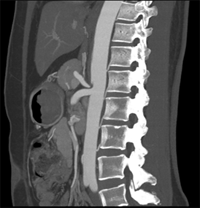

同一病人利用容積數(shù)據(jù)進(jìn)行三維處理后,高品質(zhì)MPR和三維圖像上則清晰顯示了縱向排列的腹腔干與腸系膜上動(dòng)脈相鄰近,血管發(fā)生變 異,近端血管閉塞,為臨床提供了精確的診斷信息。